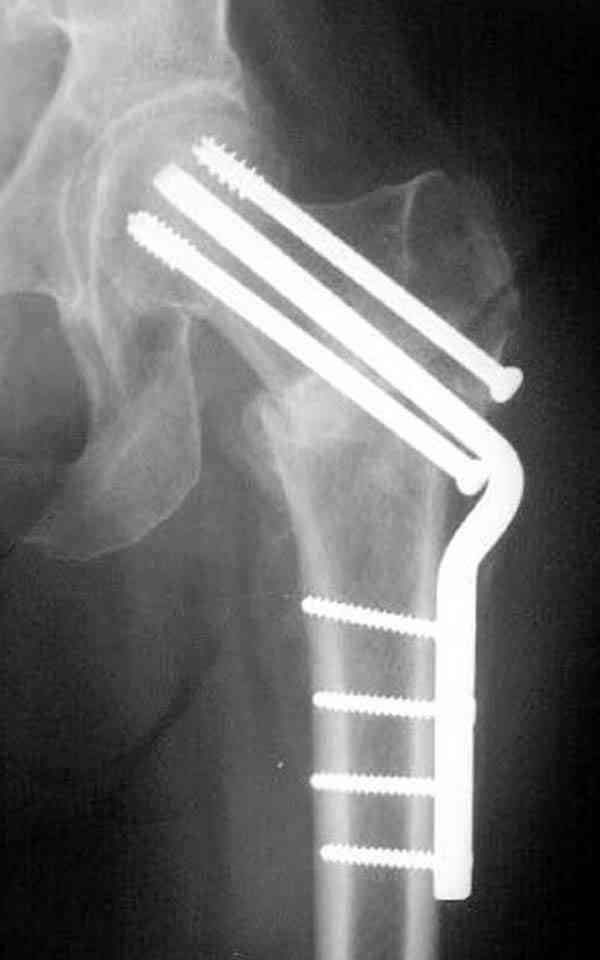

Уважаемый Антон! У меня было всего три клинических наблюдения, снимки были продемонстрированы на московской конференции. Количества этих снимков хватило для подачи заявки, а затем и получения патента на изобретение. В свое время РОСПАТЕНТ потребовал подтверждения методики клиническими наблюдениями. У одной из больных действительно произошла повторная травма, и произошел подвертельный перелом на стороне армированной шейки бедренной кости (см. снимки). Это подтвердило основную идею изобретения - была сохранена и головка, и армированная шейка бедренной кости. Но тут не обошлось безпроблем. Анестезиологи отказались давать наркоз, а провести остеосинтез под м/а пластиной и винтом DHS не согласилась больная. Дальнейшее лечение скелетным вытяжением. На контр. Рентгенограмме через 2 месяца признаки формирования костной мозоли. Повторных обращений двух других пациентов не было. Для более детальных исследований и выводов необходимо значительно большее количество клинических наблюдений. Такие исследования могли быть проведены в условиях клиник медуниверситета. Напомню, я работаю в травмотделении провинциальной городской больницы. Насчет экспертов страховых компаний, так пусть они выскажут свое мнение. Армирование кости - это плановые операции по желанию больного, какие здесь могут быть противоречия? На армирование все больные, к моему удивлению, согласились довольно легко и сразу, поэтому остеосинтез и армирование были проведены в течение одной операции. С уважением А.М.

В идеале для профилактики рефрактуры шурупы надо вводить не больше, чем под 130 градусным углом и не ниже уровня малого вертела.

Насчет биомеханических преимуществ одного шурупа тоже возникает вопрос. Если придерживаться канонов механики, для перелома шейки необходимо 3 паралельных шурупа, расположенных ближе к кортикальному слою шейки.

Предлагая методику армирования, мы рассматривали вероятность ослабления кортикального слоя в месте проведения имплантата. В перспективе, эта проблема должна быть решена формой имплантата, путем добавления к винту диафизарной накладки длиной 6-8 см, через проксимальное отверстие которой будет введен канюлированный винт, в дистальной отверстие введен монокортикальный и лучше блокируемый винт диаметром не более 3,5 мм.